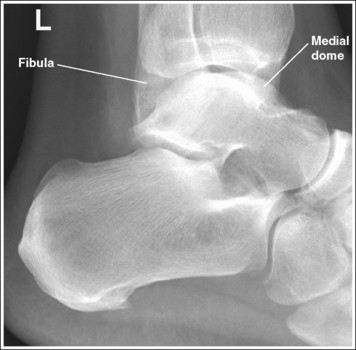

The ankle is in a lateral projection. The domes of the talus are superimposed, the tibiotalar joint is open, and the distal fibula is superimposed by the posterior half of the distal tibia.

• To obtain a lateral ankle projection, begin with the patient in a supine position, with the leg extended (Figure 6-57) and the foot dorsiflexed until its long axis forms a 90-degree angle with the lower leg. Rotate the patient and affected leg until the lateral foot surface is against the IR, and then adjust the degree of rotation until the surface is aligned parallel with the IR (Figure 6-58). For most patients, this positioning places the lower leg parallel with the imaging table. If this is not the case, as with a patient with a large upper thigh, the foot and IR should be elevated until the lower leg is parallel with the imaging table.

• Effect of lower leg positioning on talar dome superimposition. Often, if the knee is not fully extended (Figure 6-59) or if the distal tibia is not elevated to place the lower leg parallel with the IR in a patient with large upper thighs, the proximal tibia is positioned farther from the imaging table than the distal tibia. The resulting image demonstrates the lateral talar dome proximal to the medial talar dome and the height of the longitudinal arch appears less than it actually is because the cuboid shifts anteriorly and the navicular bone moves posteriorly in this position and the talocalcaneal joint will be narrowed (see Image 43). If the distal tibia is positioned farther from the table than the proximal tibia, the medial talar dome is demonstrated proximal to the lateral dome, and the height of the longitudinal arch appears greater than it actually is because the cuboid shifts posteriorly and the navicular bone moves anteriorly in this position and the talocalcaneal joint will be widened (see Image 44). When viewing a lateral ankle projection that demonstrates one of the talar domes proximal to the other, evaluate the height of the longitudinal arch and the degree of talocalcaneal joint visualization to determine which dome is the proximal dome. If the navicular bone is superimposed over more of the cuboid than expected and a narrowed talocalcaneal joint is seen, the lateral dome is the proximal dome. If the navicular bone is superimposed over less of the cuboid than expected and a wider talocalcaneal joint is seen, the medial dome is the proximal dome.

• Effect of foot positioning on talar dome superimposition. To demonstrate accurate AP alignment of the talar domes, position the lateral surface of the foot parallel with the IR. If this surface is not parallel with the IR, the talar domes are demonstrated one anterior to the other. When the leg is rotated more than needed to place the lateral foot surface parallel with the IR (leg externally rotated), as shown in Figure 6-60, the medial talar dome is demonstrated anterior to the lateral talar dome (see Image 45). If the leg is not rotated enough to place the lateral foot surface parallel with the IR (leg internally rotated), as shown in Figure 6-61, the medial talar dome is demonstrated posterior to the lateral talar dome (see Image 46). When taking a lateral ankle projection that demonstrates one of the talar domes anterior to the other, observe the position of the fibula in relation to the tibia to determine how the patient should be repositioned. On most lateral ankle projections with accurate positioning, the fibula is positioned in the posterior half of the tibia. On a lateral projection with poor positioning, if the fibula is demonstrated more posteriorly, the medial dome is anterior and the patient was positioned with the forefoot depressed and the heel elevated (leg externally rotated), as shown in Figure 6-60. If the fibula is demonstrated more anteriorly, the medial domes are posterior and the patient was positioned with the forefoot elevated and the heel depressed (leg internally rotated), as shown in Figure 6-61.

The long axis of the foot is positioned at a 90-degree angle with the lower leg.

• In most cases, when the patient is relaxed, the foot rests in plantar flexion. Plantar flexion results in a forced flattening of the anterior pretalar fat pad, reducing its usefulness in the detection of joint effusion (see Image 47). Consequently, it is best to dorsiflex the patient's foot, placing its long axis at a 90-degree angle with the lower leg. This positioning also places the tibiotalar joint in a neutral position and helps prevent the leg from rolling too far anteriorly. Anterior foot rotation elevates the heel and rotates the foot.